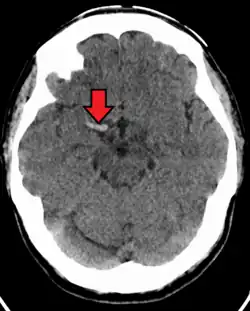

| CT scan without intravenous contrast showing hyperdense aspect of the right middle cerebral artery, indicating thrombus within the vessel | |

The dense MCA sign is a dense artery sign observed on non-contrast computed tomography (CT) of the brain and is an important early marker of acute ischemic stroke involving the middle cerebral artery territory.[1] It refers to an abnormally increased attenuation (hyperdensity) of the MCA, reflecting an intraluminal thrombus or embolus. This sign is also referred to as the hyperdense MCA sign.

The dense MCA sign is caused by a fresh thrombus or embolus occluding the lumen of the middle cerebral artery. A thrombus with a high concentration of red blood cells and fibrin has increased density relative to normal flowing blood, leading to its hyperattenuating appearance on a non-contrast CT scan.

Dense MCA sign stands for a hyperdense linear structure located along the course of the middle cerebral artery (MCA), typically in the Sylvian fissure in CT images. The sign may be seen unilaterally (on the affected side) compared to the contralateral MCA, which appears of normal attenuation. The sign is most commonly observed in the M1 segment of the MCA and less commonly in distal branches (M2/M3 segments), where it is termed the hyperdense MCA dot sign.[2] The comparison of thrombus with the unaffected side improves diagnostic accuracy.[3]